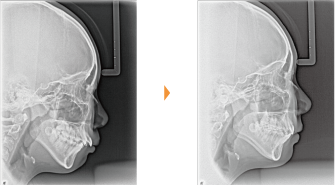

| 主訴 | 前歯が出ている |

| 年齢・性別 | 35歳 / 女性 |

| 治療方針 | 叢生も前歯の突出も大きいケース。小臼歯抜歯だけでは改善できないため、大臼歯の抜歯も行なった。 |

| 抜歯部位 | 上下顎左右小臼歯、左上第1大臼歯(計5本) |

| 使用装置 | マルチブラケット装置 |

| 治療期間 | 36か月 |

| リテーナー | 上顎インビジブル、フィックス、下顎インビジブル |

| 費用 | 885,000円(税別) |